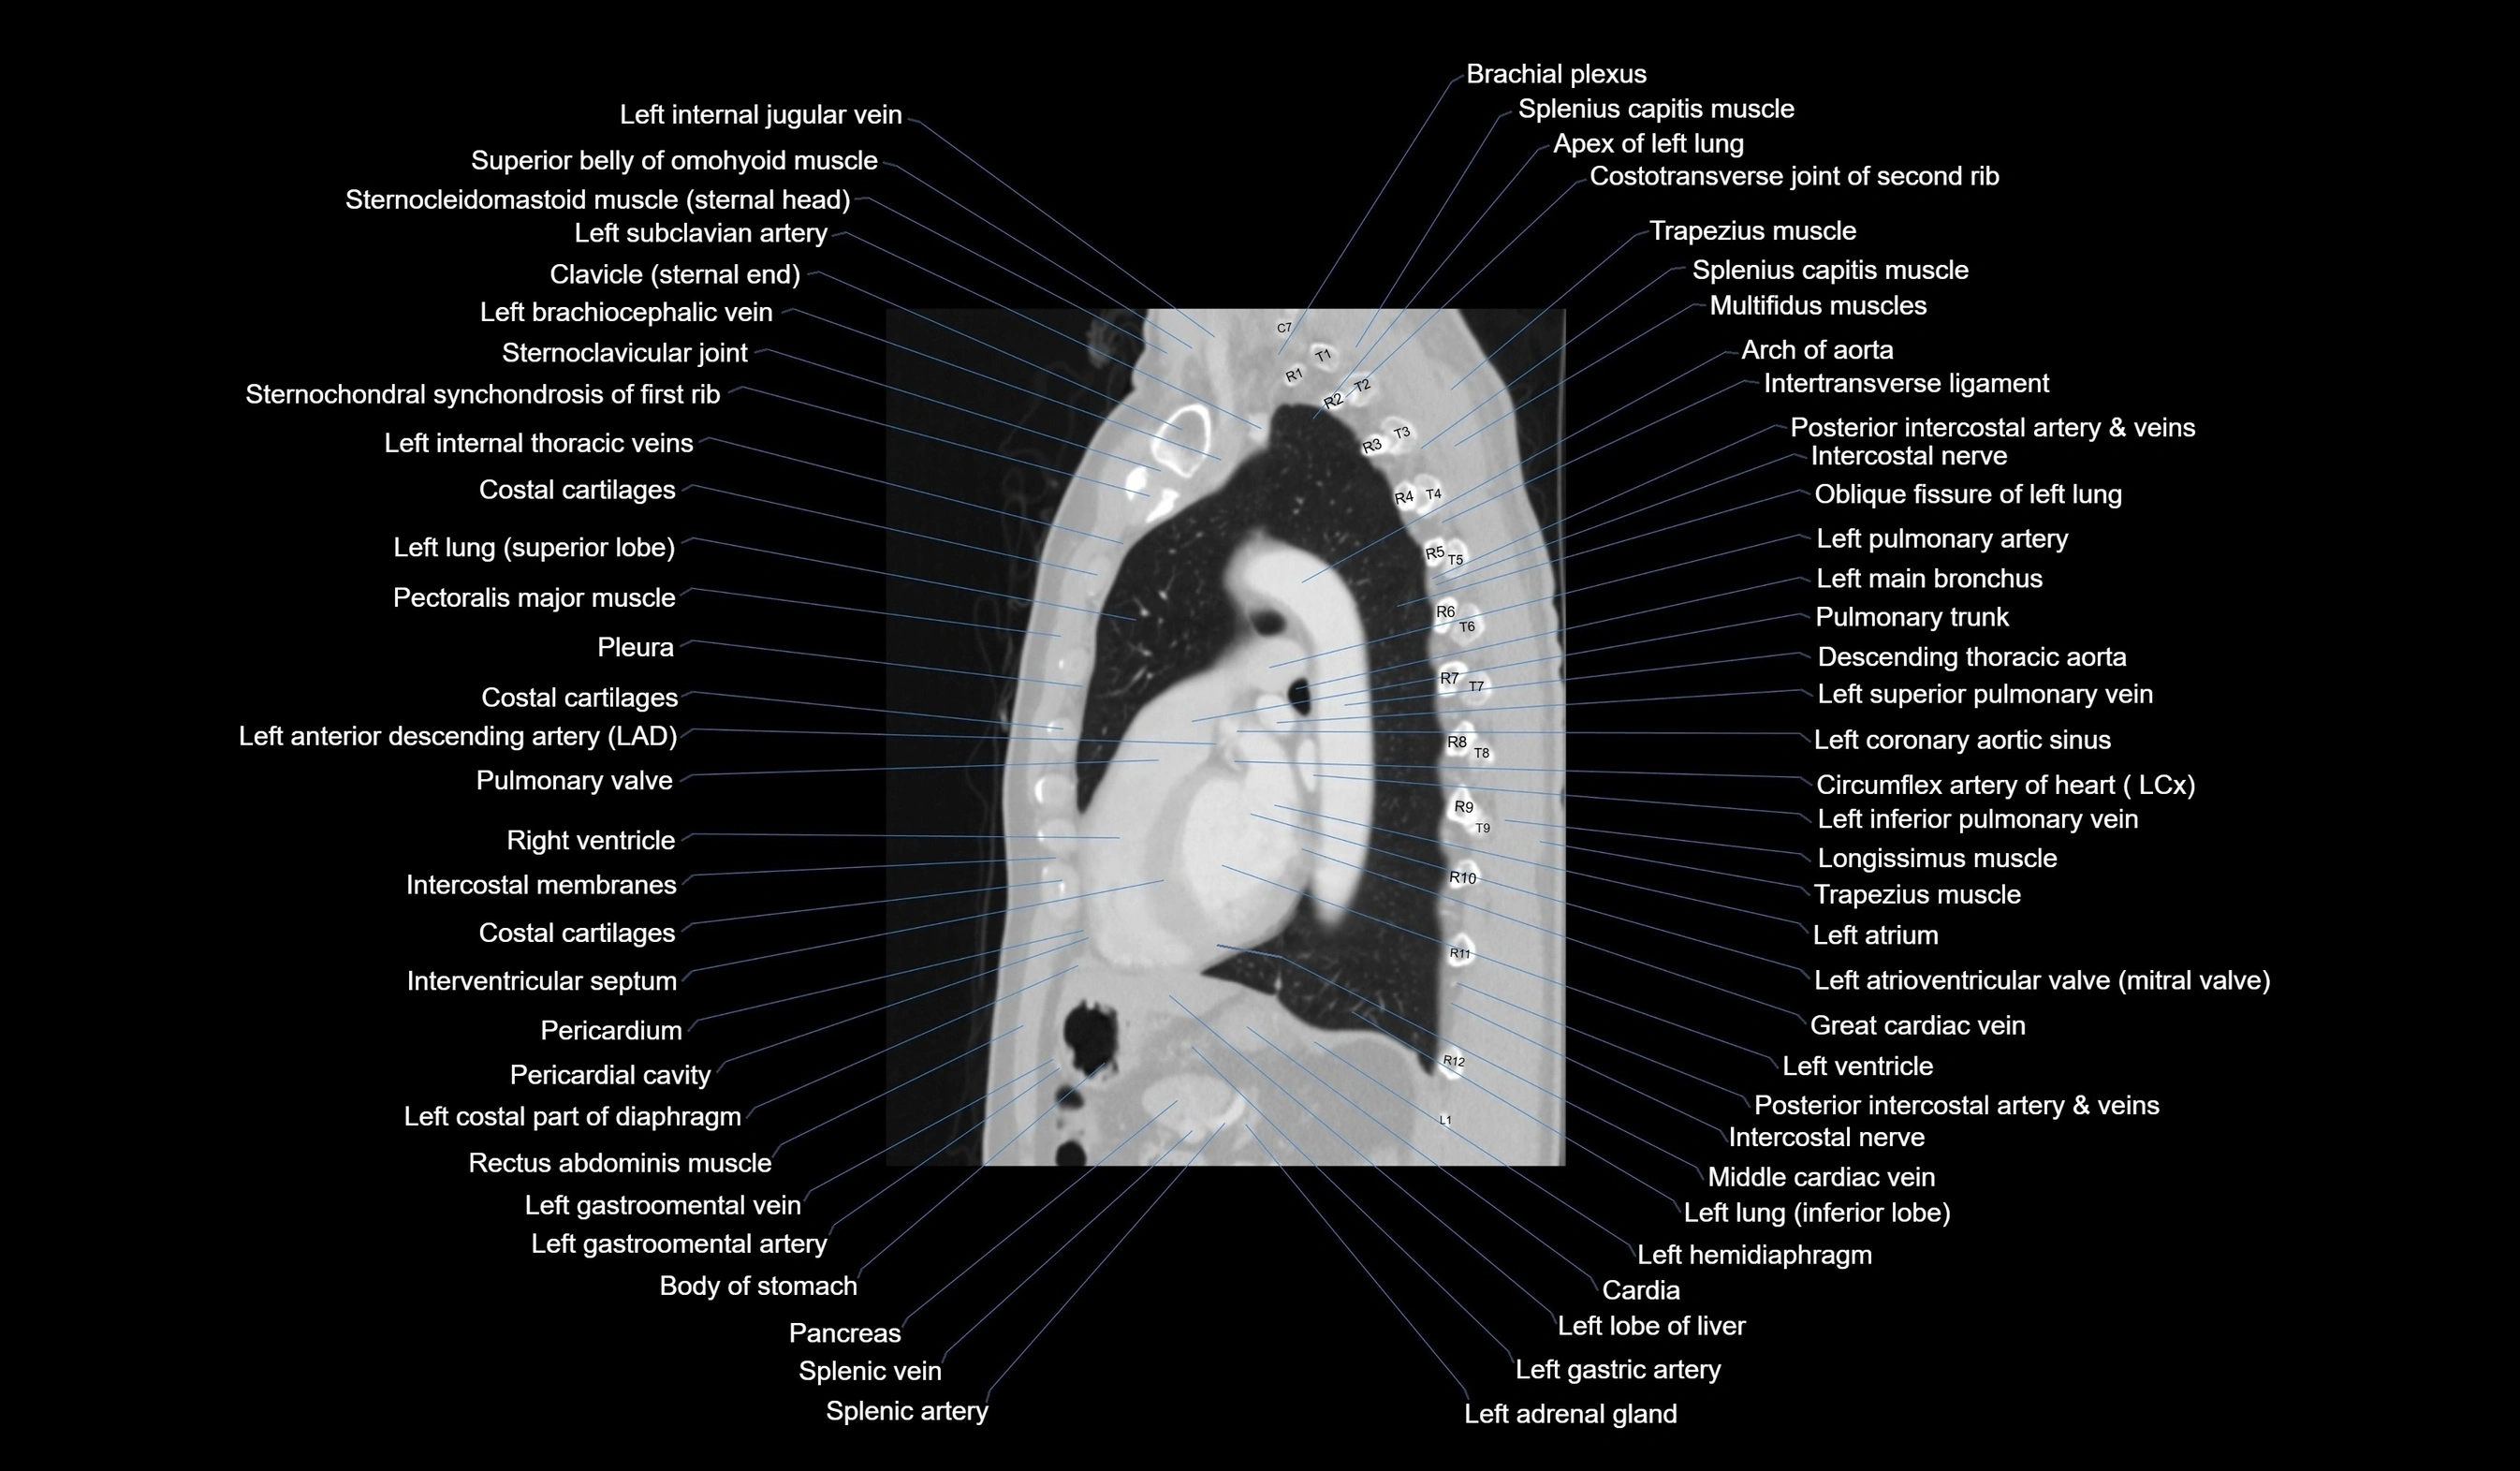

- Left anterior descending artery (LAD)

- Left atrioventricular valve (mitral or bicuspid valve)

- Left atrium

- Left gastric artery

- Left gastro-omental (gastroepiploic) vein

- Left hemidiaphragm

- Left lobe of liver

- Left main bronchus

- Left pulmonary artery

- Left superior pulmonary vein

- Left ventricle

- Pancreas

- Pericardium

- Pulmonary trunk

- Pulmonary valve

- Spleen

- Splenic artery

- Splenic vein